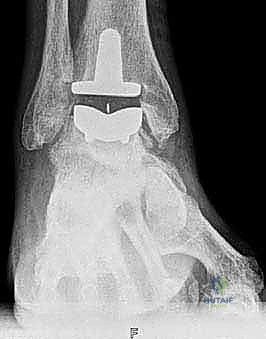

4. تركيب المفصل الصناعي (Implantation)

يتكون مفصل الكاحل الصناعي الحديث عادة من ثلاثة أجزاء:

* قطعة معدنية علوية: تُثبت في عظمة الظنبوب (الساق).

* قطعة معدنية سفلية: تُثبت في عظمة الكاحل.

* قطعة بلاستيكية (بولي إيثيلين عالي الكثافة): توضع بين القطعتين المعدنيتين لتنزلق بسلاسة وتمتص الصدمات، محاكيةً وظيفة الغضروف الطبيعي.

يتم تثبيت هذه الأجزاء بإحكام (إما عن طريق الضغط المباشر لتشجيع نمو العظم حولها، أو باستخدام أسمنت طبي خاص).